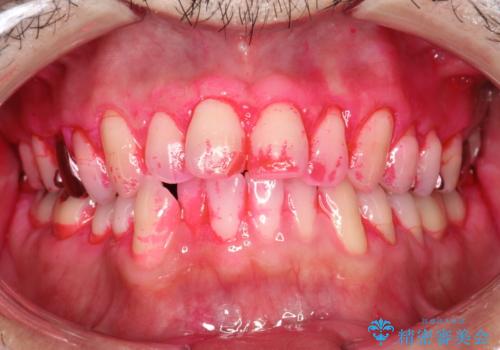

- 夜間の歯ぎしり・食いしばり予防のナイトガードを作成希望とのことで来院されました。しばらくクリーニングも受けていないとのことでPMTC30分コースを行いました。

プラークや歯石により、歯肉が炎症している場合、歯と歯肉の境目が鮮明に型取り出来ないなどがあります。そのため、マウスピースの作成前などには、PMTCで歯の表面の汚れを落とすことで、仕上がりのマウスピースがより精密なものとなります。